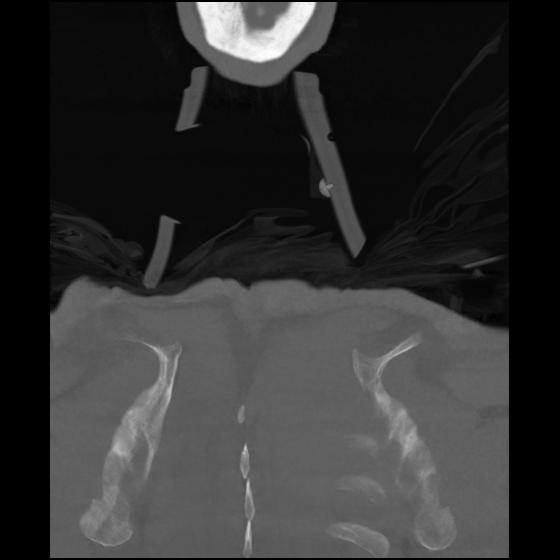

23 ANGIO,CE,Cor-MIP,5.000,ANGIO,Cor-MIP,